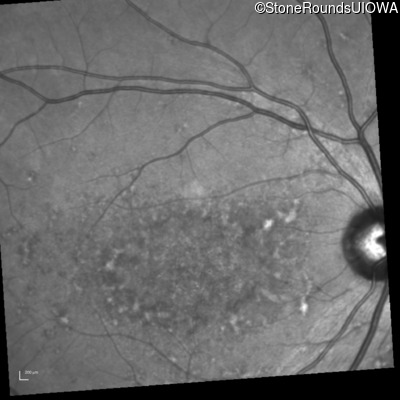

AR Stargardt Disease (IIA)

This 22 year old woman first had difficulty seeing the blackboard at age 14 and this was not correctable with glasses.

Age at visit: 17 years

Age at visit: 18 years

Age at visit: 19 years

Age at visit: 22 years